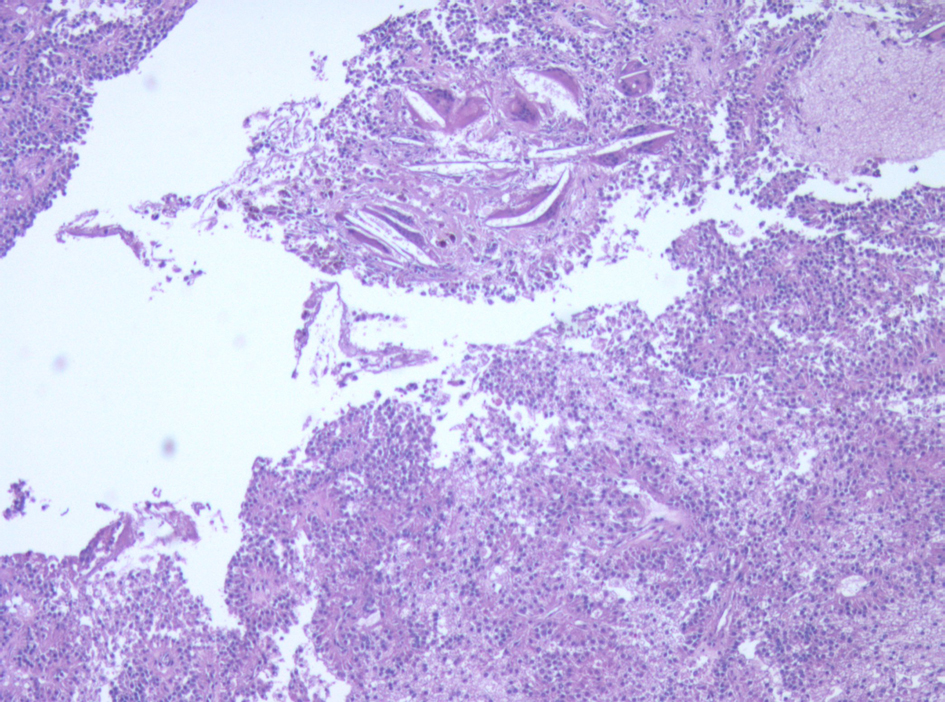

Surveillance AUS was performed biannually, then annually. A surveillance AUS performed 43 months post-operatively demonstrated fatty transformation of the liver with a discrete hypoechoic lesion measuring 1.1 × 1.0 × 0.8 cm in segment 4B/5 of the liver. There was no evidence of local recurrence. The patient was asymptomatic, with no focal findings on physical exam. Laboratory studies including liver function tests were within normal limits. Magnetic Resonance Imaging (MRI) demonstrated a 1-cm lesion in segment 4B, and a 0.8 cm lesion in segment 5 of the liver (Fig. 4). Both lesions demonstrated intermediate high signal on T2 weighted images and progressive enhancement after gadolinium injection. They demonstrated restricted diffusion on diffusion weighted imaging. They were suspicious for metastases, but atypical hemangiomas remained in the differential. In order to narrow this differential, a contrast enhanced ultrasound study was performed, and the lesions demonstrated mild arterial enhancement with rapid complete washout in keeping with metastases. These lesions were not avid on Fluorodeoxyglucose-Positron Emission Tomography (FDG-PET). The patient underwent for a diagnostic laparoscopy and US-guided biopsy of her hepatic lesions. A definitive diagnosis could not be made intra-operatively based on intra-operative frozen section analysis of the needle biopsy, however the pathologist favored malignancy rather than a benign etiology. Therefore, the procedure was converted to a laparotomy with resection of segments 4b and 5, as well as a cholecystectomy. An enlarged periportal lymph node was excised as well. Pathology revealed 2 foci of metastatic solid pseudopapillary tumor of the pancreas in the liver (Fig. 5), measuring 8 mm and 7 mm. The enlarged lymph node was negative for malignancy. She recovered uneventfully from this procedure and was discharged home on POD 5.

![]() Click for large image | Figure 5. Micrograph of one of the liver metastases. The tumor demonstrates neoplastic cells supported by delicate vessels, pseudopapillary growth pattern, and cholesterol clefts. |